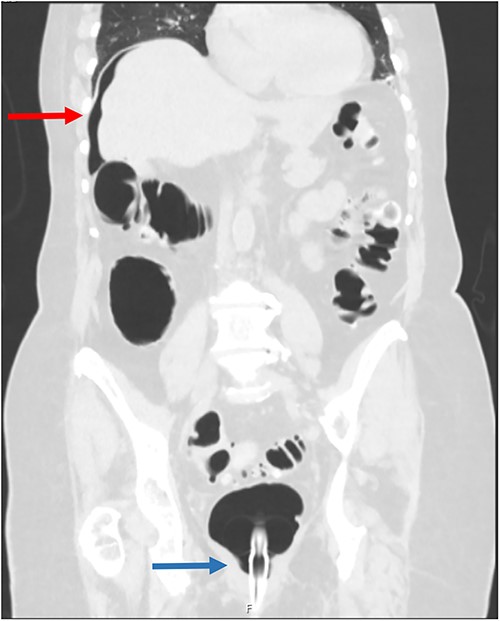

An 85-year-old female was referred from a peripheral hospital with large volume pneumoperitoneum detected during CTC (Fig. 1). CTC was performed using automated gas insufflation via a Foley catheter. Pneumoperitoneum was detected immediately after gas insufflation, therefore the CTC was abandoned. Despite the radiological findings, on review she was asymptomatic, without abdominal pain, tachycardia or fever. Her past medical history was significant for sigmoid diverticulitis, with no previous history of abdominal surgery. She underwent an incomplete colonoscopy 3 weeks prior, abandoned due to tortuous sigmoid colon anatomy. Despite being asymptomatic, she underwent diagnostic laparoscopy due to the large volume of pneumoperitoneum. At laparoscopy she was found to have a large caecal tear with two small areas of non-viable serosa (Fig. 2), and no gross intra-abdominal contamination. She proceeded to a laparoscopic right hemicolectomy with a subsequent uneventful post-operative recovery and benign histopathology.

Coronal CT scan following gas insufflation; the red arrow points to pneumoperitoneum above the liver, and the blue arrow points to a rectal catheter.